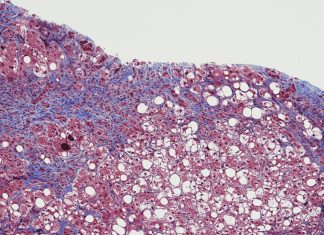

Hepatitis C deaths fall sharply but cure access dropping

The introduction of direct-acting antivirals therapies for hepatitis C in 2016 has contributed to a 20% decline in deaths attributed to the disease, but...